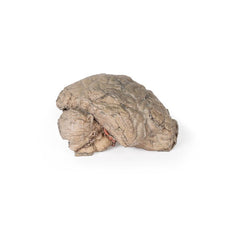

3D Printed Brain Hemisection

3D Printed Brain Hemisection

This 3D model is a midsagittal hemisection through a whole brain, preserving the right side anatomy and deep brain

structures and spaces visible in the midline. In lateral view, the right cerebral and cerebellar hemispheres are

covered in the arachnoid mater. In the midline view, the brain regions from the cerebrum to the medulla oblongata

are preserved. Centrally, the third ventricle is opened, with an intact septum pellucidum superiorly positioned and

obscuring the lateral ventricles within the cerebral hemisphere. On the inferior margin of the third ventricle both

the right mamillary body and right optic tract can be observed, whereas posteriorly the cerebral aqueduct can be

observed extending across the midbrain between the tectum and tegmentum towards the fourth ventricle (between the

cerebellum and pons). The cerebellum is separated from the occipital lobe by a preserved portion of the tentorium

cerebelli, and in cross-section the cerebellar cortex helps form the prominent arbor vitae.